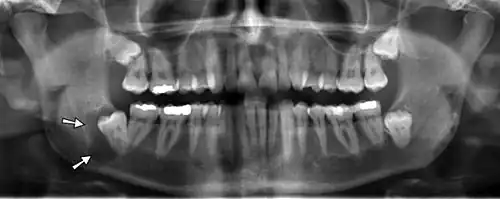

Panoramic radiographs have the capability to demonstrate a portion of the neck and display atheromas (calcifications in the carotid artery) which are an indication of both local and generalized (systemic) atherosclerosis. Atherosclerosis of the coronary arteries leading to myocardial infarction (heart attack), and atherosclerosis of the carotid artery leading to stroke are the number one and number three most common causes of death in the United States.[6]

Additional research projects have further determined the prevalence rate of these atheromas in the general population (3–5%)[8][9] and among high-risk groups (over 25% in: recent stroke victims,[10] individuals with obstructive sleep apnea syndrome,[11][12][13] postmenopausal women,[14] type 2 diabetics,[15][13][16] individuals with dilated cardiomyopathy,[17][13] and among individuals who have received radiotherapy directed at the neck,[18][19]). These findings have been corroborated by other several other researchers.[20][21][22][23][13]

Atherosclerosis is attributed to risk factors that include cigarette smoking, hyperlipidemia, obesity, diabetes mellitus, and hypertension (high blood pressure). These factors, however, do not fully account for the risk of disease. Atherosclerosis has been conceptualized as a chronic inflammatory response to endothelial cell injury[24] and dysfunction possibly arising from chronic dental infection. In 2010, using the previously validated Mattila panoramic radiographic index to quantify the totality of dental infection (i.e., periapical and furcal lesions, pericoronitis sites, carious tooth roots, teeth with pulpal caries, and vertical bony defects), Friedlander's group determined that individuals with carotid artery atheromas on their panoramic radiographs had significantly greater amounts of dental infection/inflammation than atherogenic risk-matched controls devoid of radiographic atheromas.[25][26] While the Mattila index had been previously used to relate the extent of dental infection to coronary artery disease, this research is the first to link the full range of dental disease that it measures to panoramic radiographs evidencing calcified carotid artery atherosclerosis.